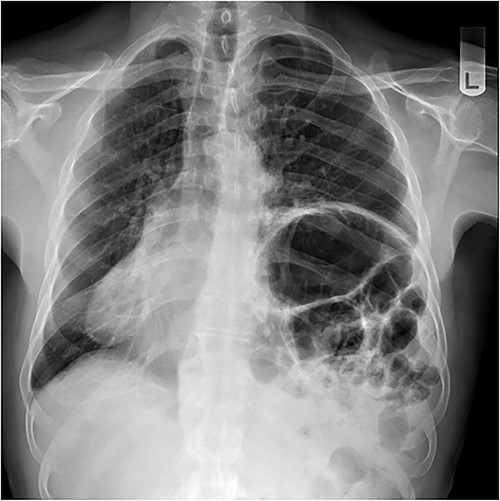

Repair was performed via Video-Assisted Thoracoscopic Surgery with an 8 cm access incision and a 5 mm camera port. The central lax portion of the diaphragm was staple resected using an Ethicon stapler followed by plication of remaining redundant diaphragmatic tissue using 2/0 polypropylene running suture. Postoperative chest X-ray showed acceptable descent of the left hemidiaphragm (Fig. 2). Hospital length of stay was 7 days. Postoperative course was complicated by subcutaneous hemorrhage, and development of a left pleural effusion post discharge drained 2 weeks postoperatively by thoracentesis. He also developed severe hiccoughs, settling on a course of esomeprazole. Histology of the 13 × 5 cm resected portion of diaphragm was consistent with eventration. The patient endorsed complete resolution of symptoms at 1 year post-repair and was seen at 2 years post-repair with no issues (Fig. 3).